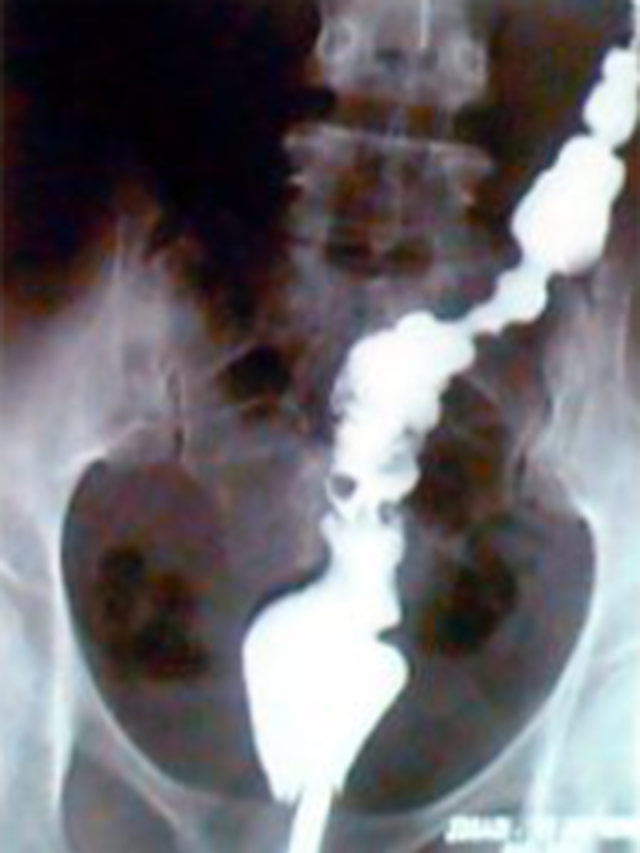

Presença de grande falha de enchimento no reto.

Imagem radiológica localizada da

falha de enchimento.

Imagem com duplo contraste mostrando

a falha de enchimento.